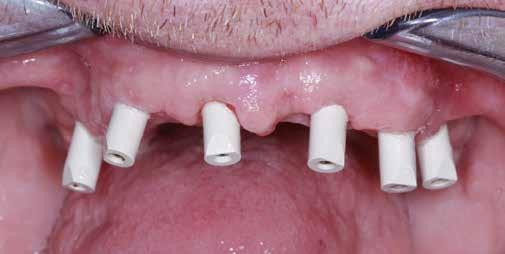

Az európai uniós rendeletekkel való harmonizáció keretében új szakvizsgák, feltételek, követelményrendszer alakult ki a hazai sztomatológiában. Megjelent az új orális implantológia szakvizsga, és egészen új szintre került a többi fogászati szakorvosi vizsga követelményrendszere is. Az új szakvizsgákhoz tartozó követelmények egyben a szakma új szabályainak is tekinthetőek, vagyis jelentős feladat elé állítják a rendelőket. A fejlődést a páciensek is nyomon követhetik az interneten keresztül, és ezzel új, és a réginél sokkal magasabb igényszintű fogászatot, implantológiát elvárásként fogalmazhatják meg. Ha ezt az új színvonalat, a fejlődést kevéssé követő fogorvosi rendelővel szemben várják el, akkor az ott végzett kezelések után kialakulhat a „konfliktus szituáció.” (1–3. képek)

Az implantológiában inkább a szájsebészeti jellegű témák voltak hangsúlyosak, a manuális eljárások dominanciája volt jellemző. Ma inkább a különleges csontpótlásokról, az előre megtervezett fogpótlásból (backwards planning = visszafelé tervezés) kiindult sebészeti tervezésről esik sok szó, ez vált követelménnyé. A digitális eljárások fölénybe kerültek a manuálisokkal szemben. A régi technológiák folyamatosan kikopnak a gyakorlatból. És itt is kérdés: Mi az, ami megfelel – még vagy már – a szakma szabályainak? Már csak emiatt is sok mindent újra kell gondolni (4–5. képek)